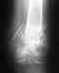

Ф.И.О. Катаев Андрей АлександровичДата рождения 15.05.1990Адрес временной регистрации Челябинская обл., г. Миасс, ул. Вернадского, 5-810Инвалид I группыИстория настоящего заболевания:24.04. 2011Получил травму при падении с высоты, лечился в г.Златоусте. с 06.05 по 11.05.2011в нейрохирургическом отделении ЧОКБ с диагнозом: осложненная спинальная травма, компрессионно-оскольчатый перелом D6, ушиб грудного отдела спинного мозга. Ушиб правого легкого.При КТ грудного отдела позвоночника и легких: картина скользящего опрокидывающегося переломовывиха D5 позвонка, компреccионно-оскольчатый перелом D6 позвонка. Гидропневмоторакс справа, ателектаз, 6,7,9,10 сегментов нижней доли правого легкого. ЯМРТ грудного отдела: мр-картина компрессии спинного мозга в сегменте D5-6, на фоне компрессионного перелома тела и переломов дуги D-6. R-графия грудной клетки: ателектаз правого легкого. Проводились санационные бронхоскопии, антибиотикотерапия. 11.05.2011г. переведен по месту жительства для лечения легочной патологии. 24.05.2011г. вновь направлен в ЧОКБ на оперативное лечение. 01.06.2011г. возвращен в ГБ№4 на долечивание из-за гипертермического синдрома, вызванного пролежнем крестца.Проведение лечебно-профилактических мероприятий и их результаты с указанием дат:Оперативное лечение 02.06.2011г. некрэктомия пролежня крестца. 15.06.2011г. эпицистостомия, 21.07.2011г. некрэктомия пролежня крестца. 30.09.2011г. вскрытие гнойного затека крестца. 04.10.2011г. вскрытие гнойного затека крестца. Медикаментозная терапия: ципрофлоксацин, аспирин, АЦЦ, лазолван, гепарин, цефтриаксон, трамадол, канефрон, сорбифер, офлоксацин, ванкомицин, цефурус, гимадес, метронидозол,Ампициллин, цефотаксим.Состояние больного:Состояние больного стабильно тяжелое. Сознание ясное, в месте и времени ориентирован. Дыхание самостоятельное, проводится во все отдела ЧДД 20. Тоны сердца ясные, ритм правильный. АД 110/70 ЧСС 72. Живот мягкий. Стул ежедневный. В области крестца пролежень 10*10 см, рана чистая, эпителизируется. Зрачки D=S движения глаз в полном объеме, лицо симметричное, язык по средней линии, глотание свободное. Сух.рефлексы рук D=S тонус и сила достаточные. С ног D=S=abc тонус снижен, сила снижена до плегии, синдром тазовых нарушений.Данныелабораторных исследований:ВИЧ 1+2 HCV, HBs Ag – отрицательный от 27.03.2012г.Сахар 5,3 молль/литр, общий белок 61, креатинин 63, ФПП 10 отриц., АЛТ 11, АСТ 11, ПТИ 60. ОАК: гемоглобин 99, эритроциты 4,4, лейкоциты 7,1, СОЭ 42, п 1%, сегм. 52, эоз. 0, лимфоциты 22, моноциты 13.ОАМ: р.1025, лейк. 25-30, эпителий 8-10, эритроциты 5,6, белок нет.Данные инструментальных исследований:R-графия лекгих от 20.01.2011г.: удлинена дуга левого желудочка очаговых и инфильтрованных теней нет.Диагноз, основное заболевание:Осложненная спинальная травма, компрессионно-оскольчатый перелом D6, ушиб грудного отдела спинного мозга. Синдром нижней параплегии с нарушением функций тазовых органов. Нейрогенный мочевой пузырь, цистостома, хронический пиелонефрит, латентное течение, ХПН 0. Гипохромная анемия легкой степени.